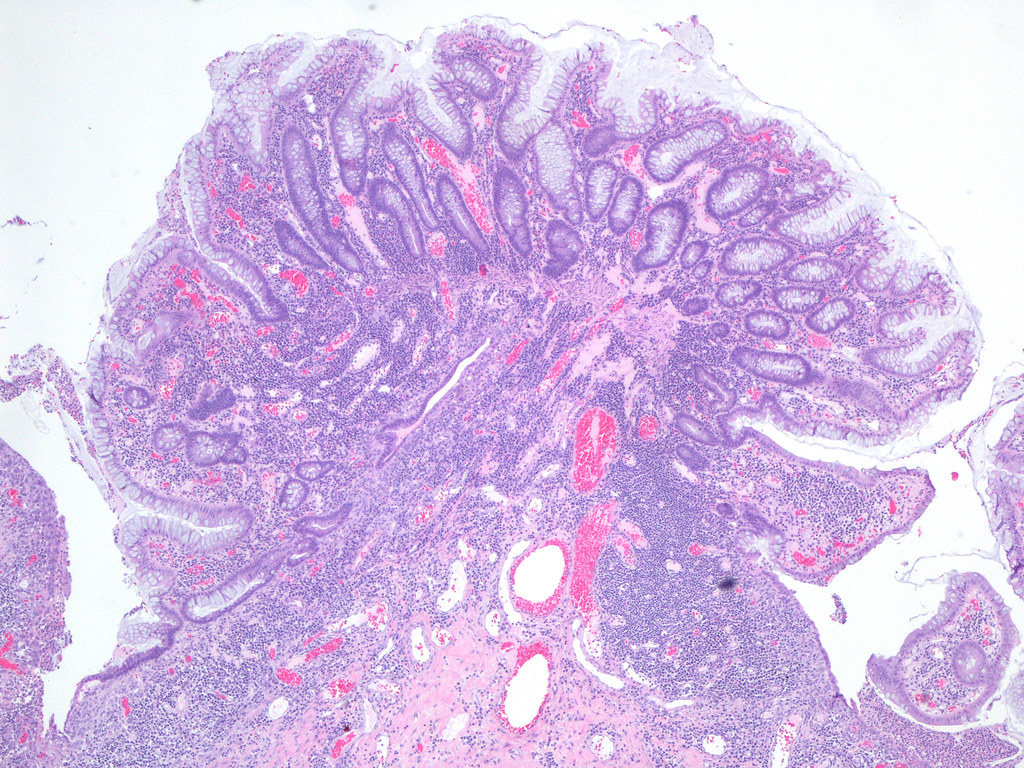

George nikias explains the common causes, symptoms and treatments for ulcerative colitis, one of the most common inflammatory bowel diseases. In inflammatory bowel disease patients, pseudopolyps are formed at the bowel wall during the inflammatory process. Web inflammatory pseudopolyps — inflammatory pseudopolyps are irregularly shaped islands of residual intact colonic mucosa that are the result of the mucosal ulceration and regeneration that occurs in response to localized or diffuse inflammation (eg, ulcerative colitis or crohn disease).

[2] there are reported cases when localized giant pseudopolyposis resulted in intestinal obstruction. These are isolated islands of intact mucosa, which are relatively raised next to denuded, ulcerated areas. The pseudopolyp is actually residual edematous mucosa sitting, like an island, on a sea of surrounding ulceration.

Web pseudopolyps pseudopolyps are polypoid protrusions into the lumen of a colon exhibiting the changes of severe ibd and are truly named, in that they are not polyps in the typical sense. Web open access abstract localized giant pseudopolyposis is an extremely rare feature of pseudopolyposis complicating inflammatory bowel disease. Symptoms of pseudopolyps are usually similar to ibd itself.

Web inflammatory polyp as a diagnosis is generally used to describe small foci of nonspecifically inflamed colonic mucosa or inflammatory pseudopolyps inflammatory polyp as a category includes several subtypes, including: It must be distinguished from inflammatory polyps, which are regions of inflamed and elevated mucosa surrounded. Endoscopically, the appearances are of multiple raised mucosal tags or polyps, which may be numerous, and adopt bizarre shapes.